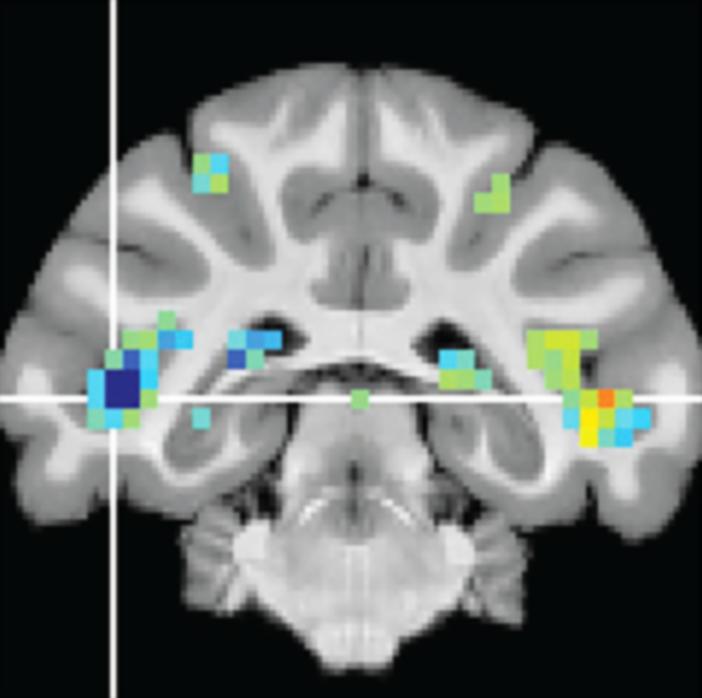

image: fMRI scans reveal activity changes in the fSTS.

Krauzlis and his colleagues described the discovery of the fSTS in a study published last year with David Leopold, Ph.D., chief of the Section on Cognitive Neurophysiology and Imaging at the National Institute of Mental Health (NIMH). Together they had the monkeys complete the visual attention tasks inside a functional magnetic resonance imaging (fMRI) machine. fMRI imaging revealed that a specific region in the temporal cortex--later named fSTS--was, like the superior colliculus, strongly activated during these attention tasks. This was surprising because this cortical region was not yet known to be important for visual attention.